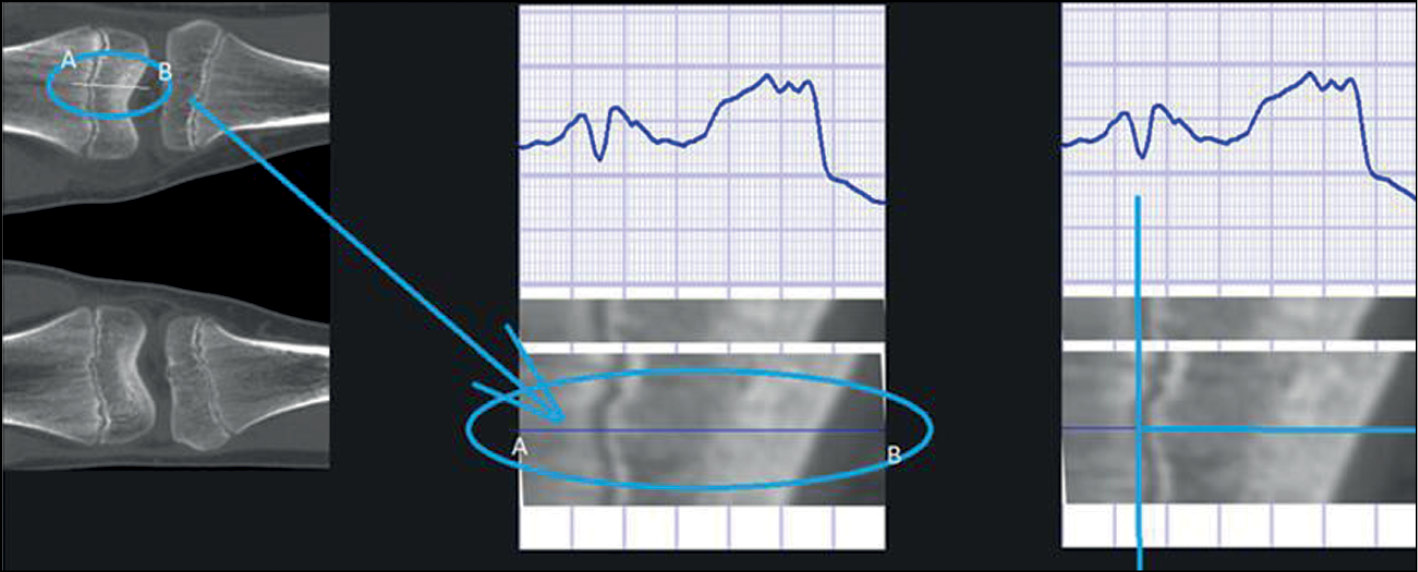

Для получения результатов и проведения первичных экспериментальных исследований, подтвердивших реализуемость, корректность и работоспособность метода, реализовано тестовое программное обеспечение с использованием искусственной нейронной сети модели YOLOv5, обученной для распознавания типов эпифизарной линии на сагиттальных проекциях. Результат анализа матрицы ошибок обучающей и тестовой выборки показал, что точность определения классов на предварительном этапе составляет порядка 80%. В процессе обучения нейронной сети было задействовано не менее 2000 объектов для каждого класса (по 10 объектов на один оптический срез, 20–25 оптических срезов на каждый случай, на каждое КТ). Этого количества достаточно для предлагаемого метода, так как основная часть оценки возраста реализуется последующей обработкой этих данных. Далее в зависимости от предварительно определённого класса возраста производятся последующая обработка областей интереса путём выполнения сегментации и распознавания, а также подсчёт процентного соотношения найденных характерных сегментов. Для каждого из типов возраста формируется два различных подкласса (для случая возраста взрослого или подростка), либо же выполняется оценка расстояния между метафизом и эпифизом (для случая возраста ребёнка). После этого выполняется финальная оценка возраста текущего случая. Пример оценки свойств эпифизарной линии представлен на рис. 2. Показано построение распределения яркости пикселей в области нормали к эпифизарной линии (такие нормали строятся для каждой точки линии, и, в свою очередь, обработка выполняется для каждой линии на каждом оптическом срезе, что и позволяет извлечь максимально возможный и объективный объём данных, в отличие от известных подходов).

Рис. 2. Механизм оценки локальных свойств каждой точки эпифизарной линии (плоскости) при расчёте возраста.

Fig. 2. The mechanism for evaluating the local properties of each point of the epiphyseal line (plane) when calculating the age.